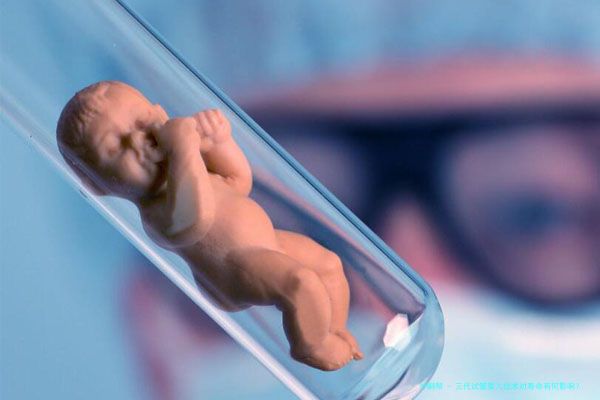

三代试管婴儿技术对生存期有何影响,在科技前行的海潮中,三代试管婴儿技术为众多夫妇圆了生育梦。然而关于这一技术是否会影响孩子生存期的担忧也随之而来。如此三代试管婴儿真的会影响孩子的寿命吗?

简言之,三代试管婴儿技术,就是胚胎移植,它通过在试验室将精子和卵子结合形成胚胎,再次把胚胎移植到女性肚子里,帮助因身体原因没有办法自然怀孕的夫妇完成生育愿望。